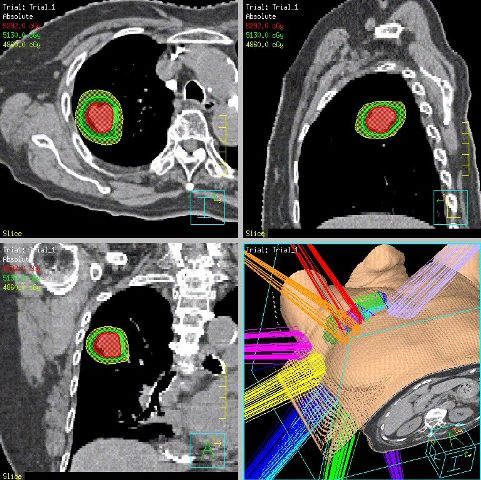

悪性腫瘍に対する放射線治療および肝腫瘍や産婦人科疾患に対する血管内治療(インターベンショナルラジオロジー)を行っています。

放射線治療装置を更新し、平成26年6月より放射線治療を再開いたしました。従来の放射線治療に加えて精度の高い先進的な放射線治療が可能となり、肺腫瘍へのピンポイント治療も行っています。